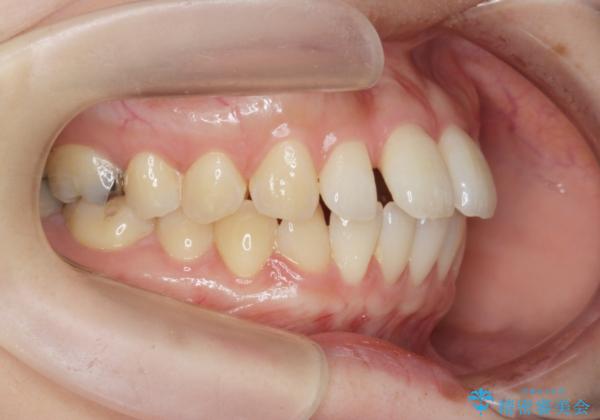

- 出っ歯に見える前歯を治したい、と矯正治療を希望され来院されました。

奥歯の噛み合わせに大きな問題はないので、目立つ前歯の角度・隙間を重点的に整え、審美的な歯並びを獲得できるよう計画します。

治療によりしっかりと前歯の角度が改善され、審美的な歯並びを手に入れることができました。